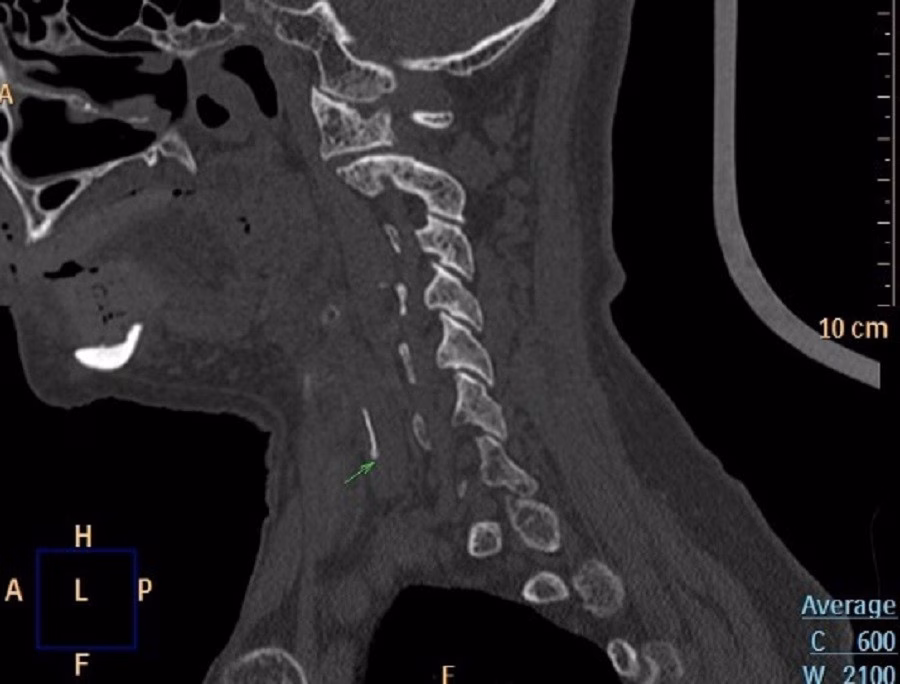

Sau vài ngày, cảm giác đau và vướng không giảm mà ngày càng nặng, khiến việc ăn uống trở nên khó khăn. Khi đến khám, nội soi Tai Mũi Họng phát hiện phù nề nghiêm trọng ở vùng sụn phễu trái. X‑quang cổ nghi ngờ có dị vật và CT xác định một mảnh xương cá khoảng 1×22 mm đã xuyên ra khỏi đường tiêu hóa và cắm sâu vào thùy trái tuyến giáp.